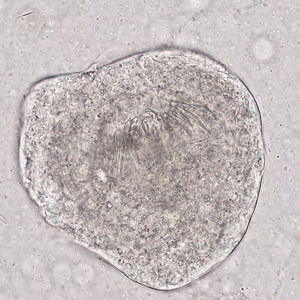

Case #321 – April, 2012

A 55-year-old man from the Middle East presenting with chronic abdominal pain was seen by his health care provider.

Figure A